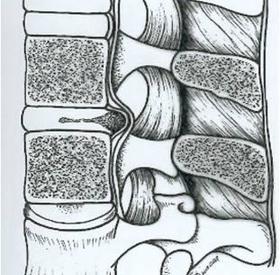

Per ernia discale lombare si intende una patologia del disco intervertebrale, quasi sempre su base degenerativa, che determina l'estrusione del nucleo polposo attraverso l'anulus fibroso (fig.1). Relativamente ai rapporti tra ernia e strutture fibrolegamentose adiacenti,…

Le patologie discali e degenerative lombari sono rappresentate essenzialmente dall'ernia discale (fig.1), dalla discopatia degenerativa (fig.2), dalla stenosi lombare (fig.3), dalla spondilolistesi degenerativa…